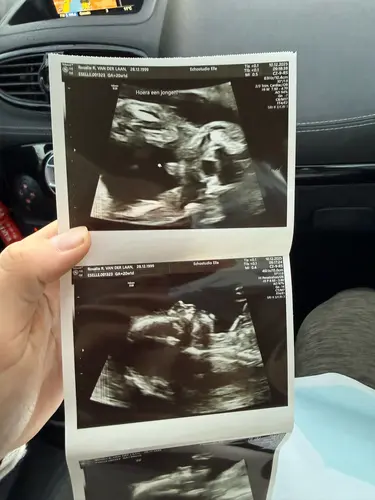

Ik heb de 20 weken echo donderdag met 19+2 馃 12 mei uitgerekend 馃┑